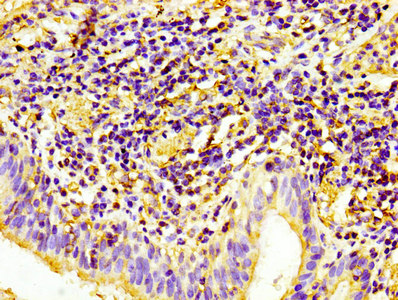

• IHC image of CSB-MA017767A0m diluted at 1:100 and staining in paraffin-embedded human lung cancer performed on a Leica BondTM system. After dewaxing and hydration, antigen retrieval was mediated by high pressure in a citrate buffer (pH 6.0). Section was blocked with 10% normal goat serum 30min at RT. Then primary antibody (1% BSA) was incubated at 4°C overnight. The primary is detected by a biotinylated secondary antibody and visualized using an HRP conjugated SP system.